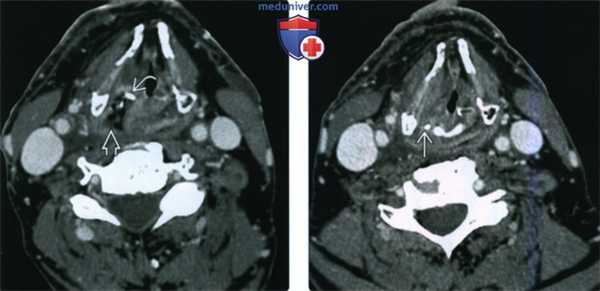

(Слева) КТ с КУ, аксиальная проекция. Пациент спустя четыре месяца после химиолучевой терапии по поводу плоскоклеточного рака гортаноглотки. Правый черпаловидный хрящ склерозирован, позади него имеется газ и мягкие ткани.

(Справа) КТ с КУ, аксиальная проекция, этот же пациент три месяца спустя. Аутоампутация правого черпаловидного хряща, от которого остался лишь небольшой костный останок. Отек в гортаноглотке значительно менее выражен. Данные признаки характерны для неопухолевого радионекроза черпаловидного хряща и тканей гортаноглотки. Хондронекроз является одним из осложнений лучевой терапии.